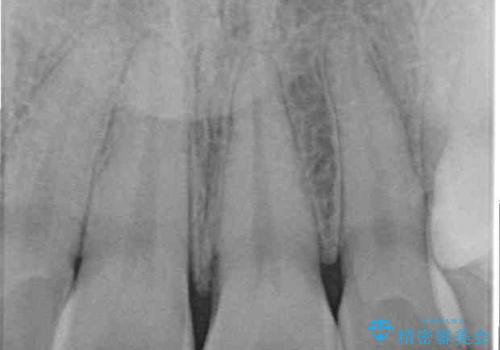

- ぶつけて欠けてしまった前歯を樹脂でつめていたものの、すり減りや変色が顕著とのことで来院された患者様です。

詰め物の詰め直しとオールセラミッククラウンの双方をご提案し、患者様ご希望によりオールセラミッククラウンにて補綴治療を行うこととしました。

歯列全体に表面の着色があったため、クリーニングとホワイトニングを事前に行い、ホワイトニング後1ヶ月ほどおいて、色の落ち着いたところで色合わせを行いました。

本物の歯のような仕上がりとなりました。